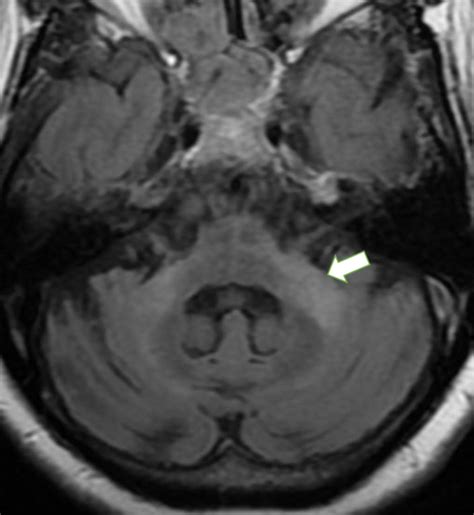

• Magnetic Resonance Imaging (MRI): MRI provides detailed images of the brain, allowing for the visualization of structural abnormalities, such as tumors, strokes, or traumatic injuries. Functional MRI (fMRI) can also be used to assess brain activity and connectivity.

• Case Study 1: Stroke: A 65-year-old patient presents with sudden onset of weakness on the right side of the body and difficulty speaking. An MRI reveals an ischemic stroke in the left cerebral peduncles brain. The patient undergoes thrombolytic therapy to dissolve the clot and is referred to a rehabilitation program for physical and speech therapy. Over time, the patient shows significant improvement in motor and language functions.

• Case Study 3: Tumor: A 40-year-old patient presents with progressive weakness and numbness on the left side of the body. An MRI reveals a tumor in the right cerebral peduncles brain. The patient undergoes surgical resection of the tumor, followed by radiation therapy. Post-surgery, the patient undergoes rehabilitation to regain motor and sensory functions, with a successful outcome.

• cerebral peduncle mri anatomy